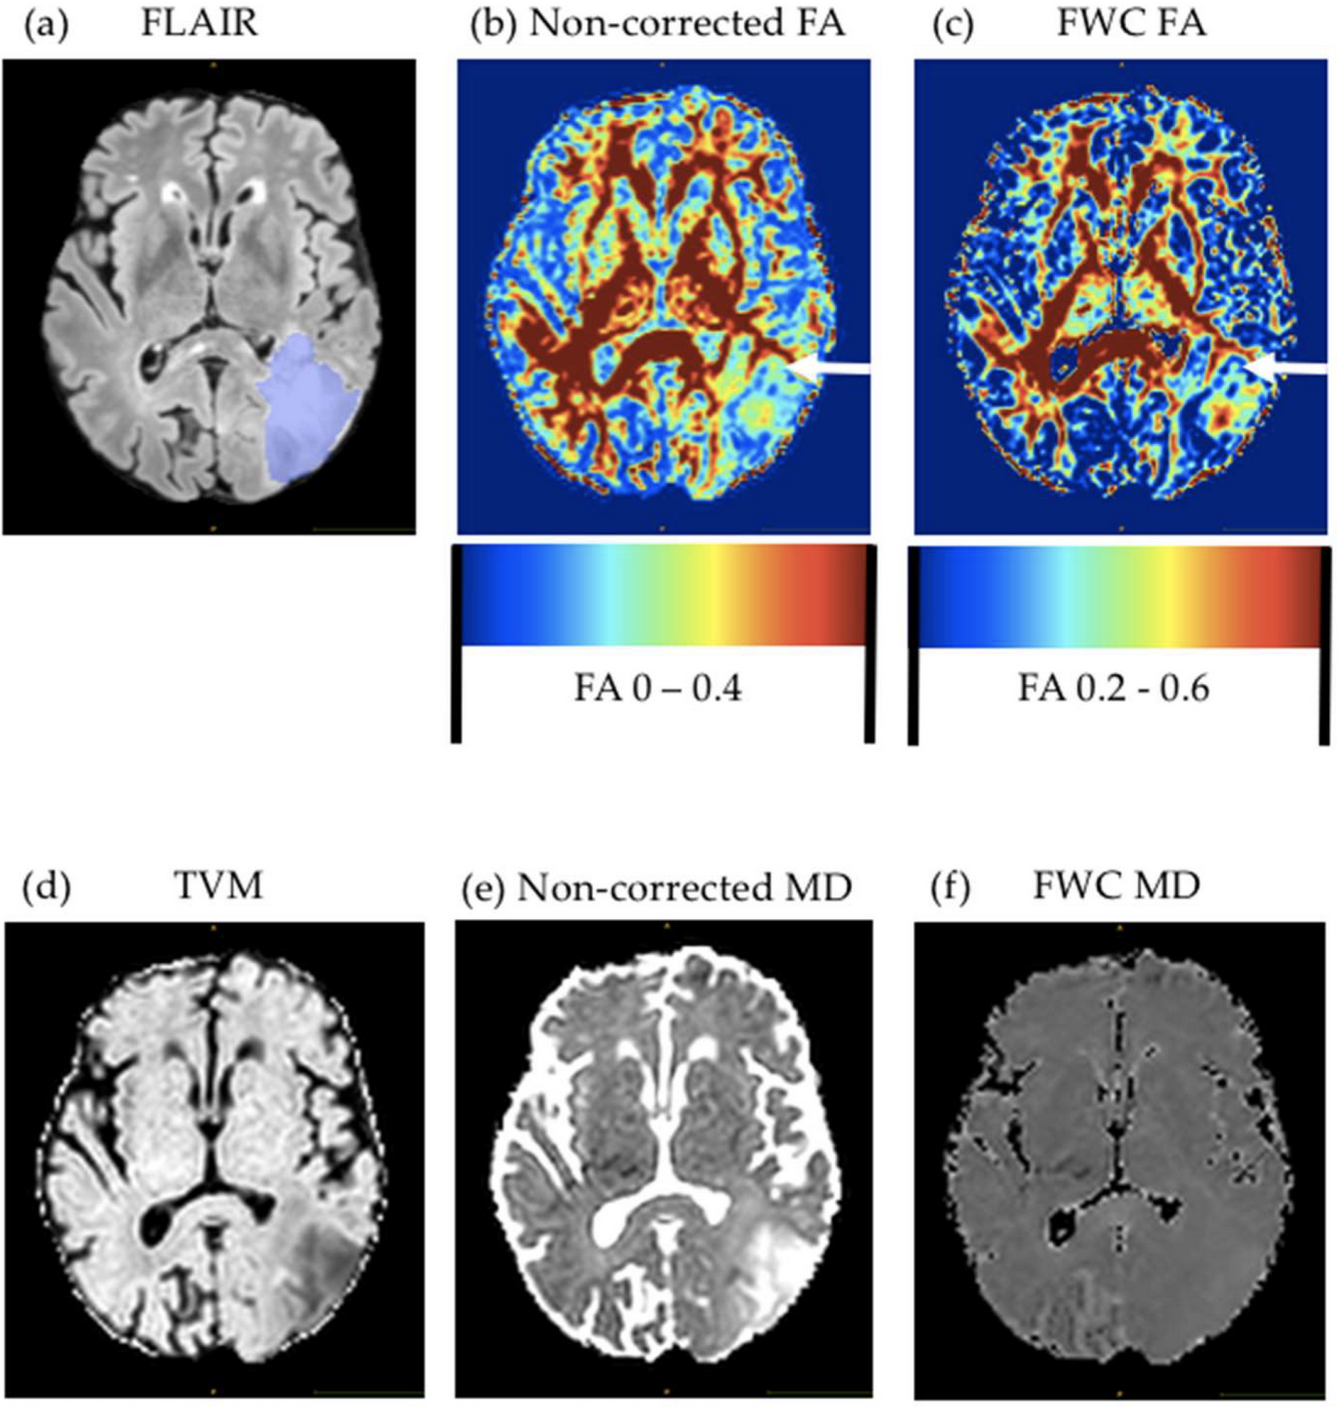

Predicting glioblastoma recurrence from preoperative MR scans using fractional-anisotropy maps with free-water suppressionMarie-Christin Metz, Miguel Molina-Romero, Jana Lipkova, Jens Gempt, Friederike Liesche-Starnecker, Paul Eichinger, Lioba Grundl, Bjoern Menze, Stephanie E Combs, Claus Zimmer, and othersCancers[ bibtex | html | abstract ]@article{metz2020predicting, title = {Predicting glioblastoma recurrence from preoperative MR scans using fractional-anisotropy maps with free-water suppression}, author = {Metz, Marie-Christin and Molina-Romero, Miguel and Lipkova, Jana and Gempt, Jens and Liesche-Starnecker, Friederike and Eichinger, Paul and Grundl, Lioba and Menze, Bjoern and Combs, Stephanie E and Zimmer, Claus and others}, journal = {Cancers}, volume = {12}, number = {3}, pages = {728}, year = {2020}, publisher = {Multidisciplinary Digital Publishing Institute}, html = {https://www.mdpi.com/669090}, abbr = {metz2020predicting.png} }Diffusion tensor imaging (DTI), and fractional-anisotropy (FA) maps in particular, have shown promise in predicting areas of tumor recurrence in glioblastoma. However, analysis of peritumoral edema, where most recurrences occur, is impeded by free-water contamination. In this study, we evaluated the benefits of a novel, deep-learning-based approach for the free-water correction (FWC) of DTI data for prediction of later recurrence. We investigated 35 glioblastoma cases from our prospective glioma cohort. A preoperative MR image and the first MR scan showing tumor recurrence were semiautomatically segmented into areas of contrast-enhancing tumor, edema, or recurrence of the tumor. The 10th, 50th and 90th percentiles and mean of FA and mean-diffusivity (MD) values (both for the original and FWC–DTI data) were collected for areas with and without recurrence in the peritumoral edema. We found significant differences in the FWC–FA maps between areas of recurrence-free edema and areas with later tumor recurrence, where differences in noncorrected FA maps were less pronounced. Consequently, a generalized mixed-effect model had a significantly higher area under the curve when using FWC–FA maps (AUC = 0.9) compared to noncorrected maps (AUC = 0.77, p < 0.001). This may reflect tumor infiltration that is not visible in conventional imaging, and may therefore reveal important information for personalized treatment decisions.